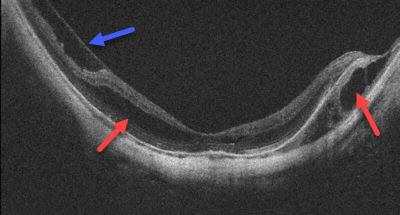

Some patients can develop splitting of the retinal tissue (macular retinoschisis) due to macular pucker, vitreomacular traction, or to the macular tissue being stretched by the elongation of the eye. This can cause central vision loss and distortion.

New blood vessel growth beneath the macula (macular neovascularization, MNV) can develop in some patients with degenerative myopia. These vessels cause the macula to swell with fluid and blood that can lead to permanent central vision loss. There are many causes of MNV including angioid streaks, choroidal rupture, idiopathic, ocular histoplasmosis, and age-related macular degeneration. Fluorescein angiography and OCT scanning help diagnosis the presence of MNV.